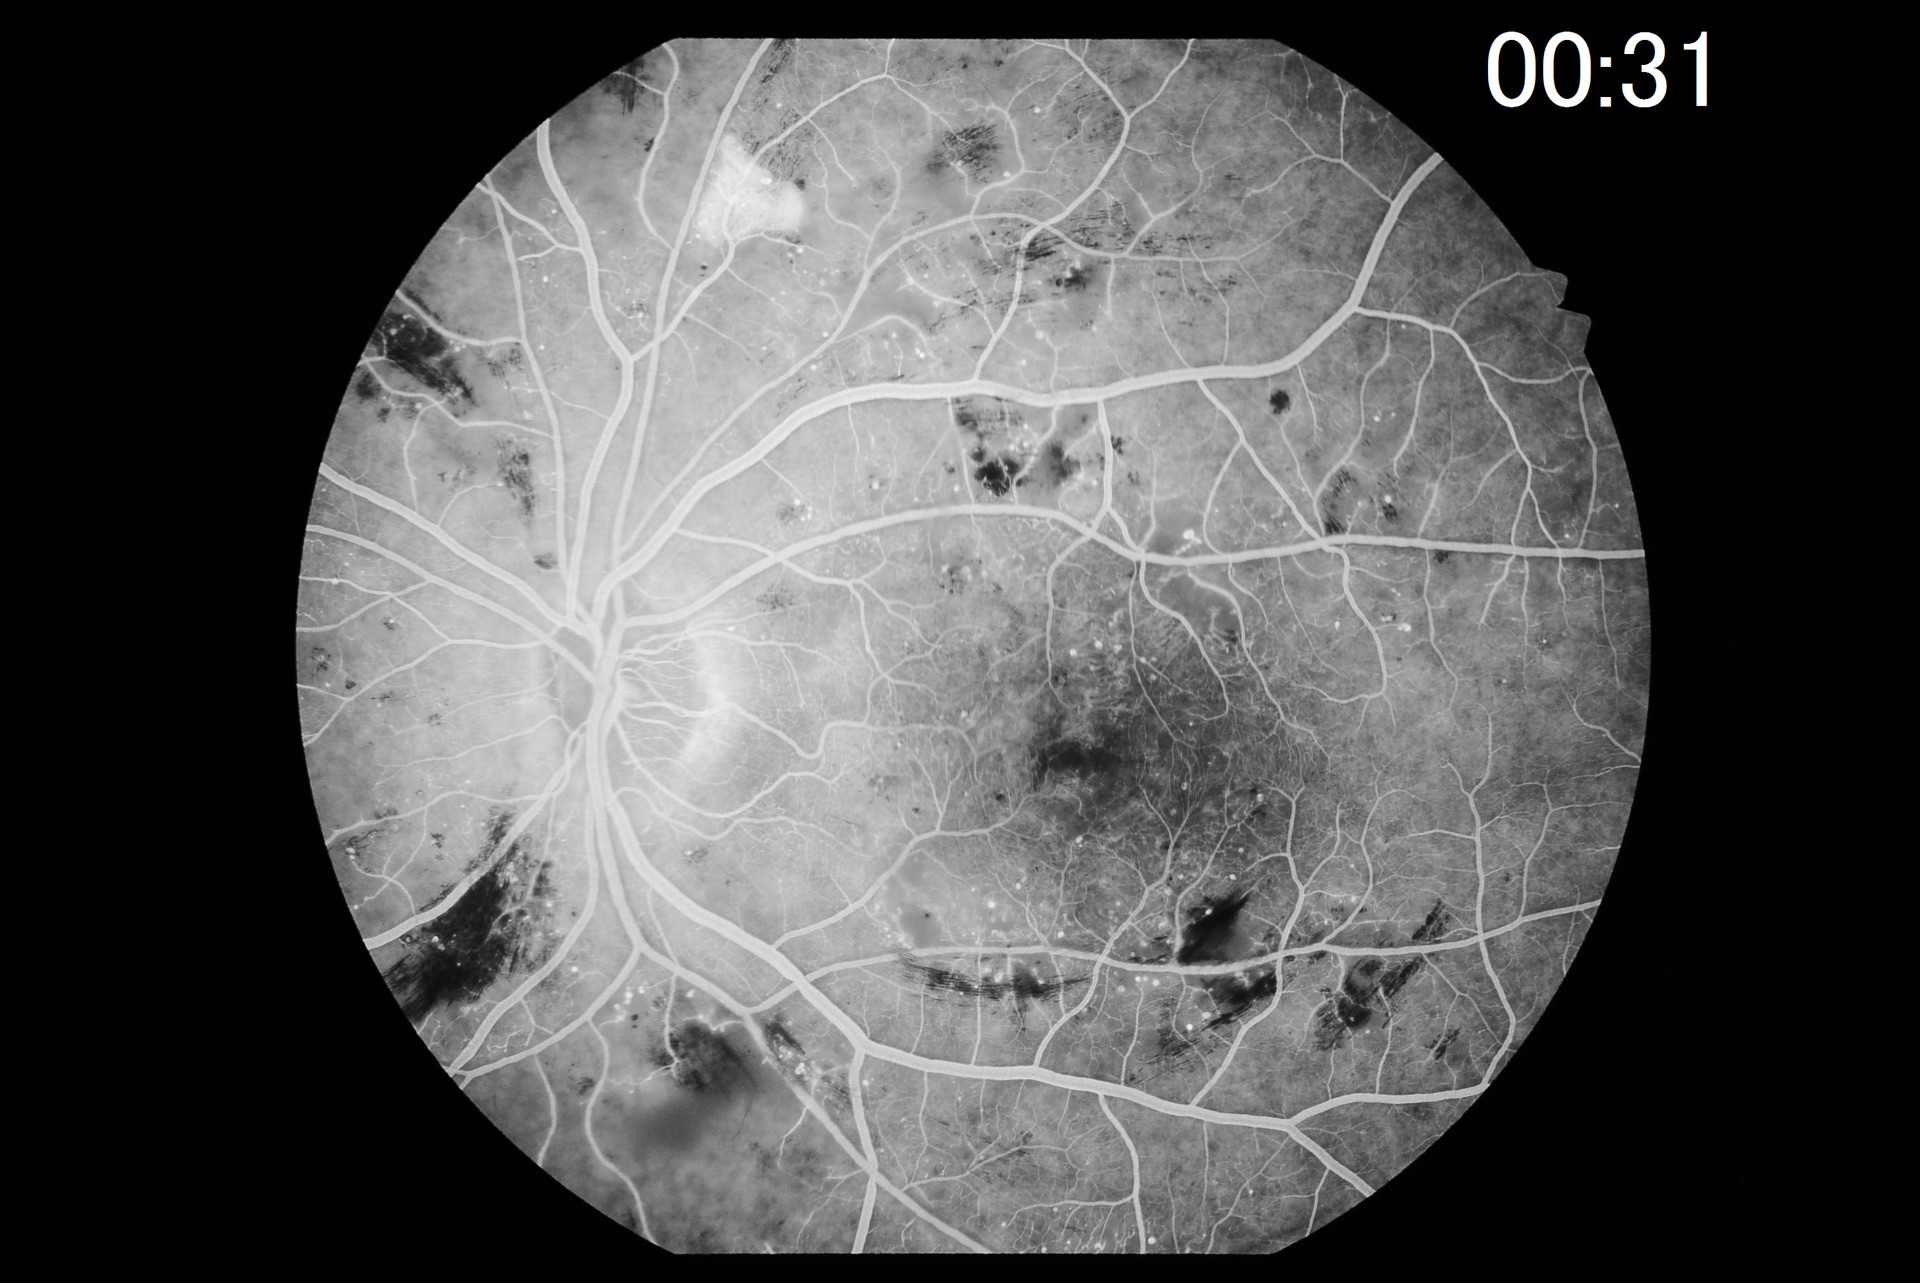

Powerful digital imaging software VK-2

With the digital imaging software VK-2, retinal images captured with the Kowa retinal camera, but also images from other sources, such as a scanner, are captured and stored quickly and easily. The input of video signals via USB is supported by switching between the instruments with 1 click. Images can be enlarged for viewing and filters (e.g. red-free filters) are available. In FA mode, the time information for each patient is displayed on the screen and several timers are available for different patients. The assembly function creates panoramic images from several fundus images.